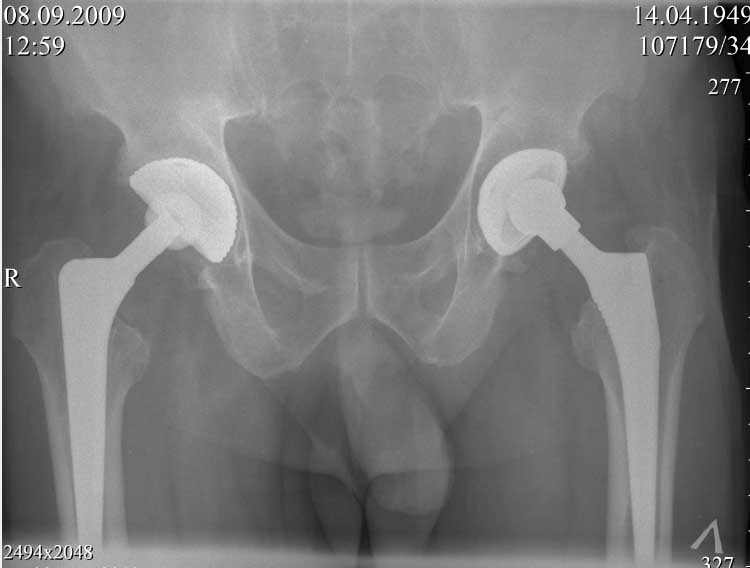

В конце 2008 года отметил боли в правой паховой области при опоре на правую ногу. На рентген снимках таза с тазобедренными суставами явных признаков нестабильности вертлужного компонента не обнаружено. В 2009 году нейрохирурги его "успешно" прооперировали на L\3-\4 связывая болевой синдром в правой паховой области с наличием грыжи указанного межпозвонкового диска. Состояние только ухудшилось, больной уже не мог долго сидеть, боль прогрессировала . Его в 2009 и 2010 годах смотрел ортопед, делались рентгенснимки, но почему то приходили к выводу что эндопротез справа стабилен. В марте 2011 года я впервые увидел его, через одну неделю после этого был прооперирован. На операции вертлужный компонент при упоре на него инструментом прокручивался во впадине и без труда был извлечен.

далее снимок в 2009 году